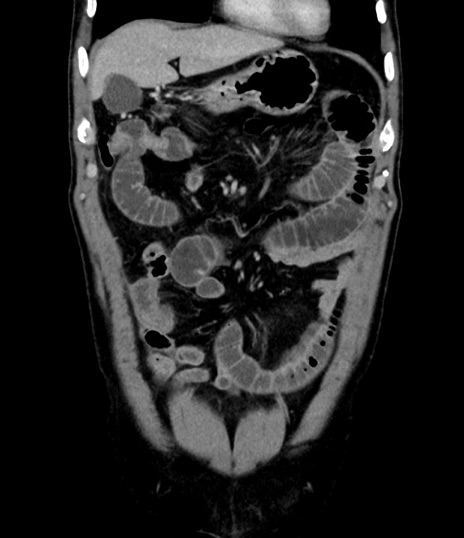

横断像

【症例】 60歳代男性

【主訴】 黒色吐物

【現病歴】 4日前から嘔気自覚、2日前の朝食後にも嘔気あり、自分で手で嘔吐反射起こし嘔吐したところ血が混ざっていたため受診。

【既往歴】 5年前汎発性腹膜炎を伴う急性虫垂炎で手術、高血圧、前立腺肥大症、高脂血症

【身体所見】 腹部正中に手術癩痕あり 腹部平坦・軟圧痛なし膨満感あり

【データ】WBC 8400、CRP 4.54